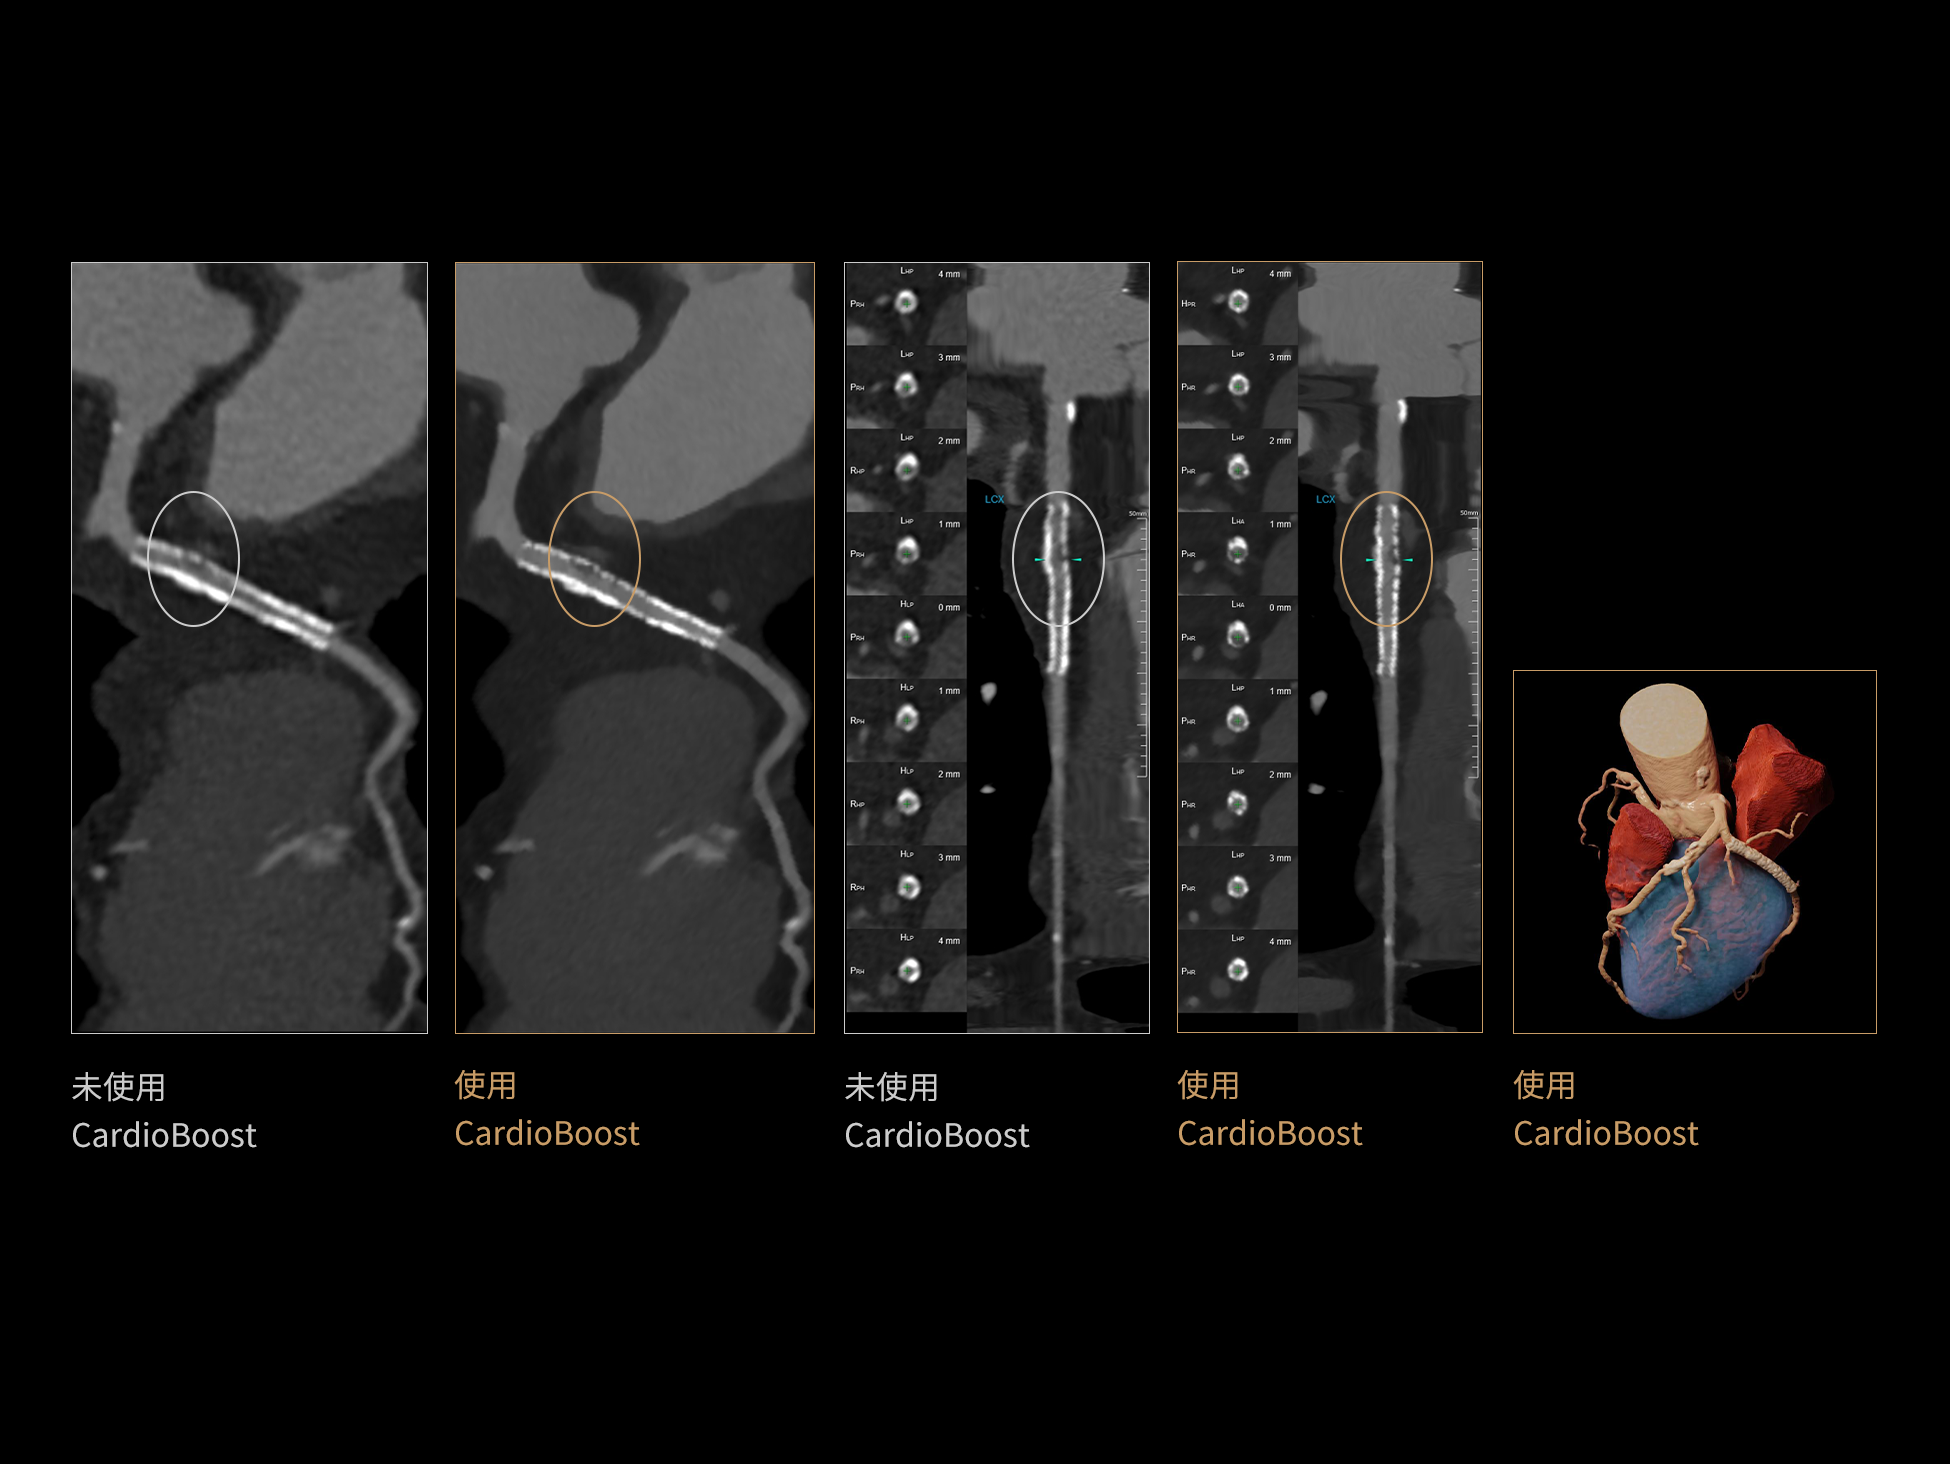

相同低对比度分辨率下

辐射剂量减少

相同辐射剂量条件下

图像噪声减少